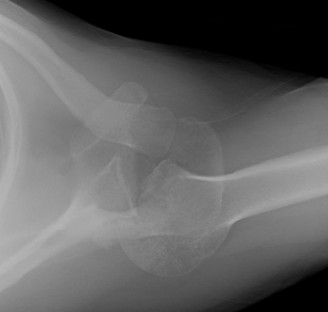

The correct answer is (A). The first step in management of this patient is obtaining a complete set of x-rays to rule out a missed shoulder dislocation (as seen in Fig. 2–45). Answers C to E describe various treatment modalities, but these cannot be instituted without a firm diagnosis. An MRA (Answer B) is most commonly used when a labral tear is suspected, but an x-ray would be the first imaging modality utilized.

Figure 2–45 Axillary view demonstrating a chronic anterior shoulder dislocation.

Chronic shoulder dislocations are relatively uncommon injuries but represent a significant challenge even for the experienced provider. There are varying opinions on what duration of time a shoulder needs to be dislocated to be termed “chronic.” Three to four weeks is a commonly accepted timeframe, although any dislocation that is not identified and treated at the time of injury can be defined as chronic. This

most frequently occurs in a polytrauma patient where other, more life-threatening injuries, may cause a provider to overlook the shoulder. Treating chronic, glenohumeral dislocations can be very challenging, so the most important goal is preventing the problem by minimizing the risk of missing an acute dislocation. This is most easily done with a complete set of x-rays on any patient with a suspected shoulder injury. Obtaining an axillary view or Vallpeau view is essential as these views will most clearly demonstrate the position of the humeral head with respect to the glenoid. An AP and even a scapular Y view are insufficient to diagnose a shoulder dislocation, and an inability to obtain a Grashey view should clue the provider into a possible dislocation.